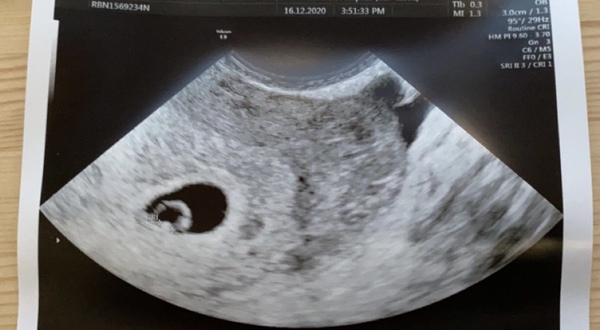

Had my first scan yesterday they haven’t gave me a due date but have said i am just over 5 weeks I was thinking I was 6 weeks by lmp 🥰